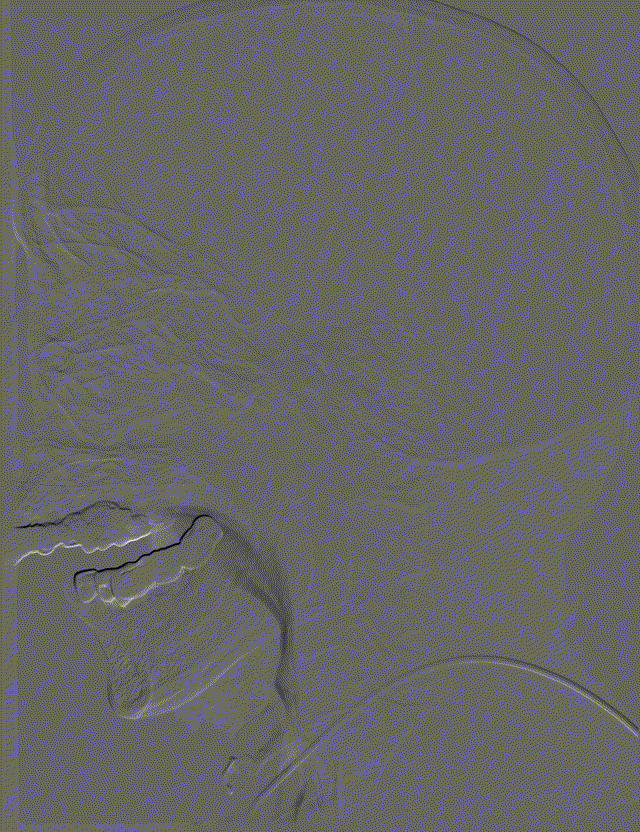

影像信息

左侧颈总动脉正侧位造影